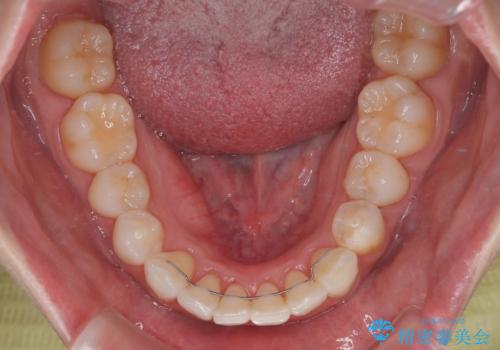

- インビザライン・モデレート

- 11ヶ月

- 2-5回